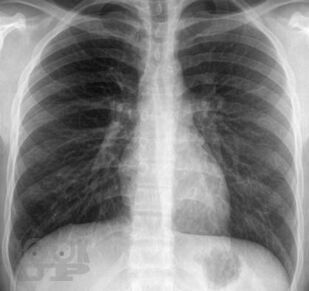

Аннотация

Монография посвящена проблемам диагностики и лечения легочной гипертензии. Термином «легочная гипертензия» объединяют группу нозологий с общим диагностическим критерием — повышением давления в легочной артерии. В работе представлены вопросы патогенеза и генетические основы легочной гипертензии, дана ее современная классификация, описаны формы легочной артериальной гипертензии, легочной гипертензии вследствие патологии левых отделов сердца, легких или хронической тромбоэмболии легочной артерии. Дан диагностический алгоритм, включающий оптимальные методы диагностики. Монография представляет современные возможности лечения легочной гипертензии, знакомит с данными ключевых рандомизированных клинических исследований и позволяет заглянуть в будущее. Работа создана специалистами ведущих экспертных центров нашей страны во главе с ФГБУ «Российский кардиологический научно-производственный комплекс» МЗ РФ и предназначена для кардиологов, пульмонологов, терапевтов, ревматологов, а также для практикующих врачей, имеющих отношение к обследованию и лечению больных с легочной гипертензией.